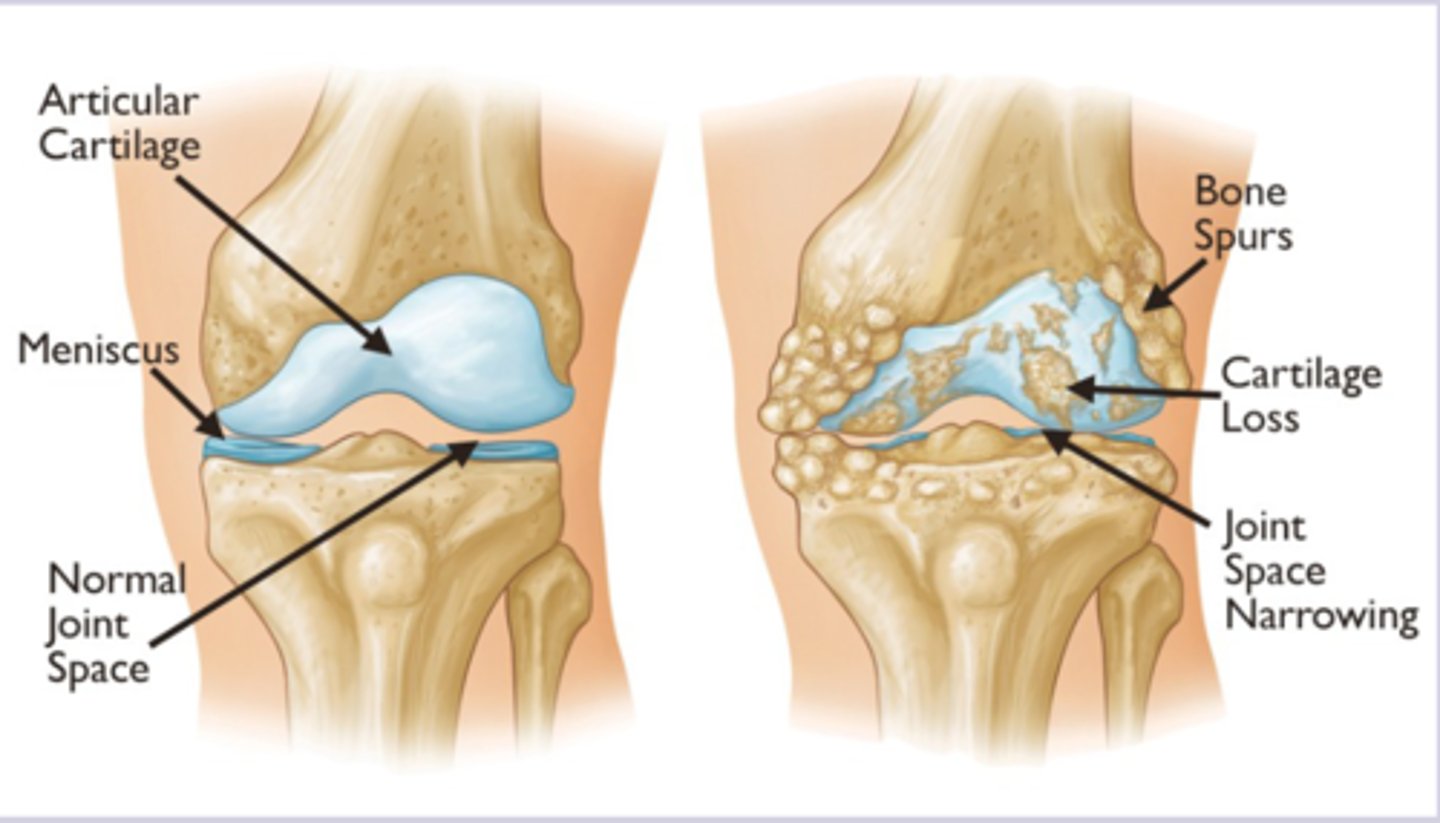

osteoarthritis patho

-progressive degradation of articular cartilage with attempted repairs mechanism > imbalance between cartilage breakdown and synthesis by chondrocytes > mechanical stress and biochemical changes create cycle of joint destruction

-subchondral bone changes

-synovial inflammation

-joint space narrowing as cartilage is lost

-Xray weight bearing: Asymmetric joint space narrowing

-subchondral sclerosis, osteophytes, subchondral cysts